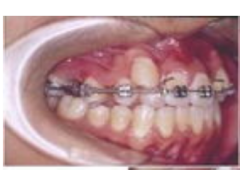

- 适用于牙齿拥挤、地包天、牙齿有缝隙、深覆盖的求美者

- 牙齿矫正术后一到两年都需要佩戴牙套,定期到医院复诊,更换牙套,直到牙齿排列整齐

- 30000-60000元/人